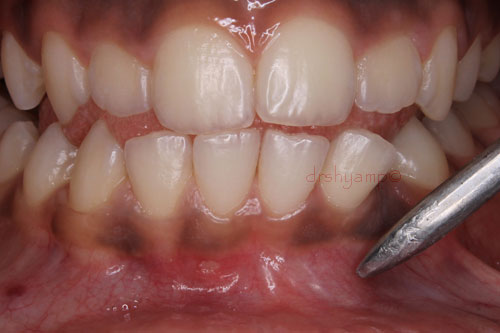

Removal of impacted canine